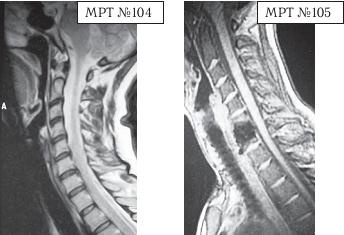

На МРТ №°103 наблюдается грыжа межпозвонкового диска в сегменте LIV-LV, частично компенсированная спондилёзом, гипертрофия задней продольной связки и выраженный эпидурит на данном уровне. В сегменте LV-SI наблюдается протрузия межпозвонкового диска, компенсированная спондилёзом. На уровне этих же сегментов наблюдается рубцовоспаечный процесс, как следствие перенесённой хирургической операции — ламинэктомии, проведённой в сегментах (LIV-LV, LV-SI), с целью устранения грыжи межпозвонковых дисков и декомпрессии спинномозговых корешков на данных уровнях. Приведённый ниже случай является показательным примером, как пациентка попала к недобросовестному хирургу, который сделал ей абсолютно необоснованную операцию. ![]() На МРТ № 104 наблюдается начальная стадия дегенеративного процесса в шейном отделе позвоночника, протрузия межпозвонкового диска в сегменте CVI—CVII. На МРТ № 105 наблюдается состояние после проведённой тотальной дискэктомии с передним межтеловым спондилодезом в сегменте CV—CVII, выпрямление физиологического лордоза, абсолютный стеноз спинномозгового канала с блоком ликворных путей, секвестрированные грыжи (с краниальной миграцией секвестров) в сегментах CIV-CV, CV-CVI, CVII-ThI. Состояние пациентки после операции ухудшилось, а в течение последующего года — значительно усугубилось. В данном конкретном случае не совсем понятно, зачем сделали эту операцию? Дооперационные жалобы больной были больше сосудистого характера. Прямых показаний к операции просто не было! Если бы данная пациентка прошла медикаментозное лечение у невропатолога, без хирургического вмешательства, то сейчас её здоровье было бы намного лучше, да и будущее бы не вызывало опасений в плане последующих осложнений. Вот ещё трагический случай во время проведения необоснованной операции. ![]() На МРТ № 106 состояние шейного отдела пациентки до операции. Наблюдается сглаженность физиологического лордоза, ликворные пути свободны, компенсированные протрузии межпозвонковых дисков в сегментах СIII—СIV На МРТ № 107 состояние шейного отдела той же пациентки после дискэктомии с межтеловым спондилодезом в сегменте CV—CVI, кроме того наблюдается травма спинного мозга на данном уровне хирургической фрезой. Если до операции у данной пациентки были незначительные вертебробазилярные нарушения, то после… Травма спинного мозга хирургической фрезой — это, конечно, трагическая случайность. Ведь от ошибок никто не застрахован и добросовестный врач никогда не даст гарантии на положительный исход любого вида лечения. Но в данном случае проведение самой операции было абсолютно необоснованным, фактически она превратила нормального человека в инвалида. Следующий пример также демонстрирует, какие бывают последствия после дискэктомии с межтеловым спондилодезом. |